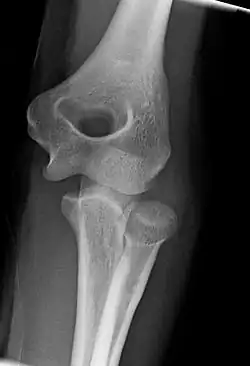

Right: AP X ray of a dislocated right elbow

There are three bones at the elbow joint, and any combination of these bones may be involved in a fracture of the elbow. Patients who are able to fully extend their arm at the elbow are unlikely to have a fracture (98% certainty) and an X-ray is not required as long as an olecranon fracture is ruled out.[27] Acute fractures may not be easily visible on X-ray.[28]

Dislocation

Elbow dislocations constitute 10% to 25% of all injuries to the elbow. The elbow is one of the most commonly dislocated joints in the body, with an average annual incidence of acute dislocation of 6 per 100,000 persons.[30] Among injuries to the upper extremity, dislocation of the elbow is second only to a dislocated shoulder. A full dislocation of the elbow will require expert medical attention to re-align, and recovery can take approximately 6 weeks.